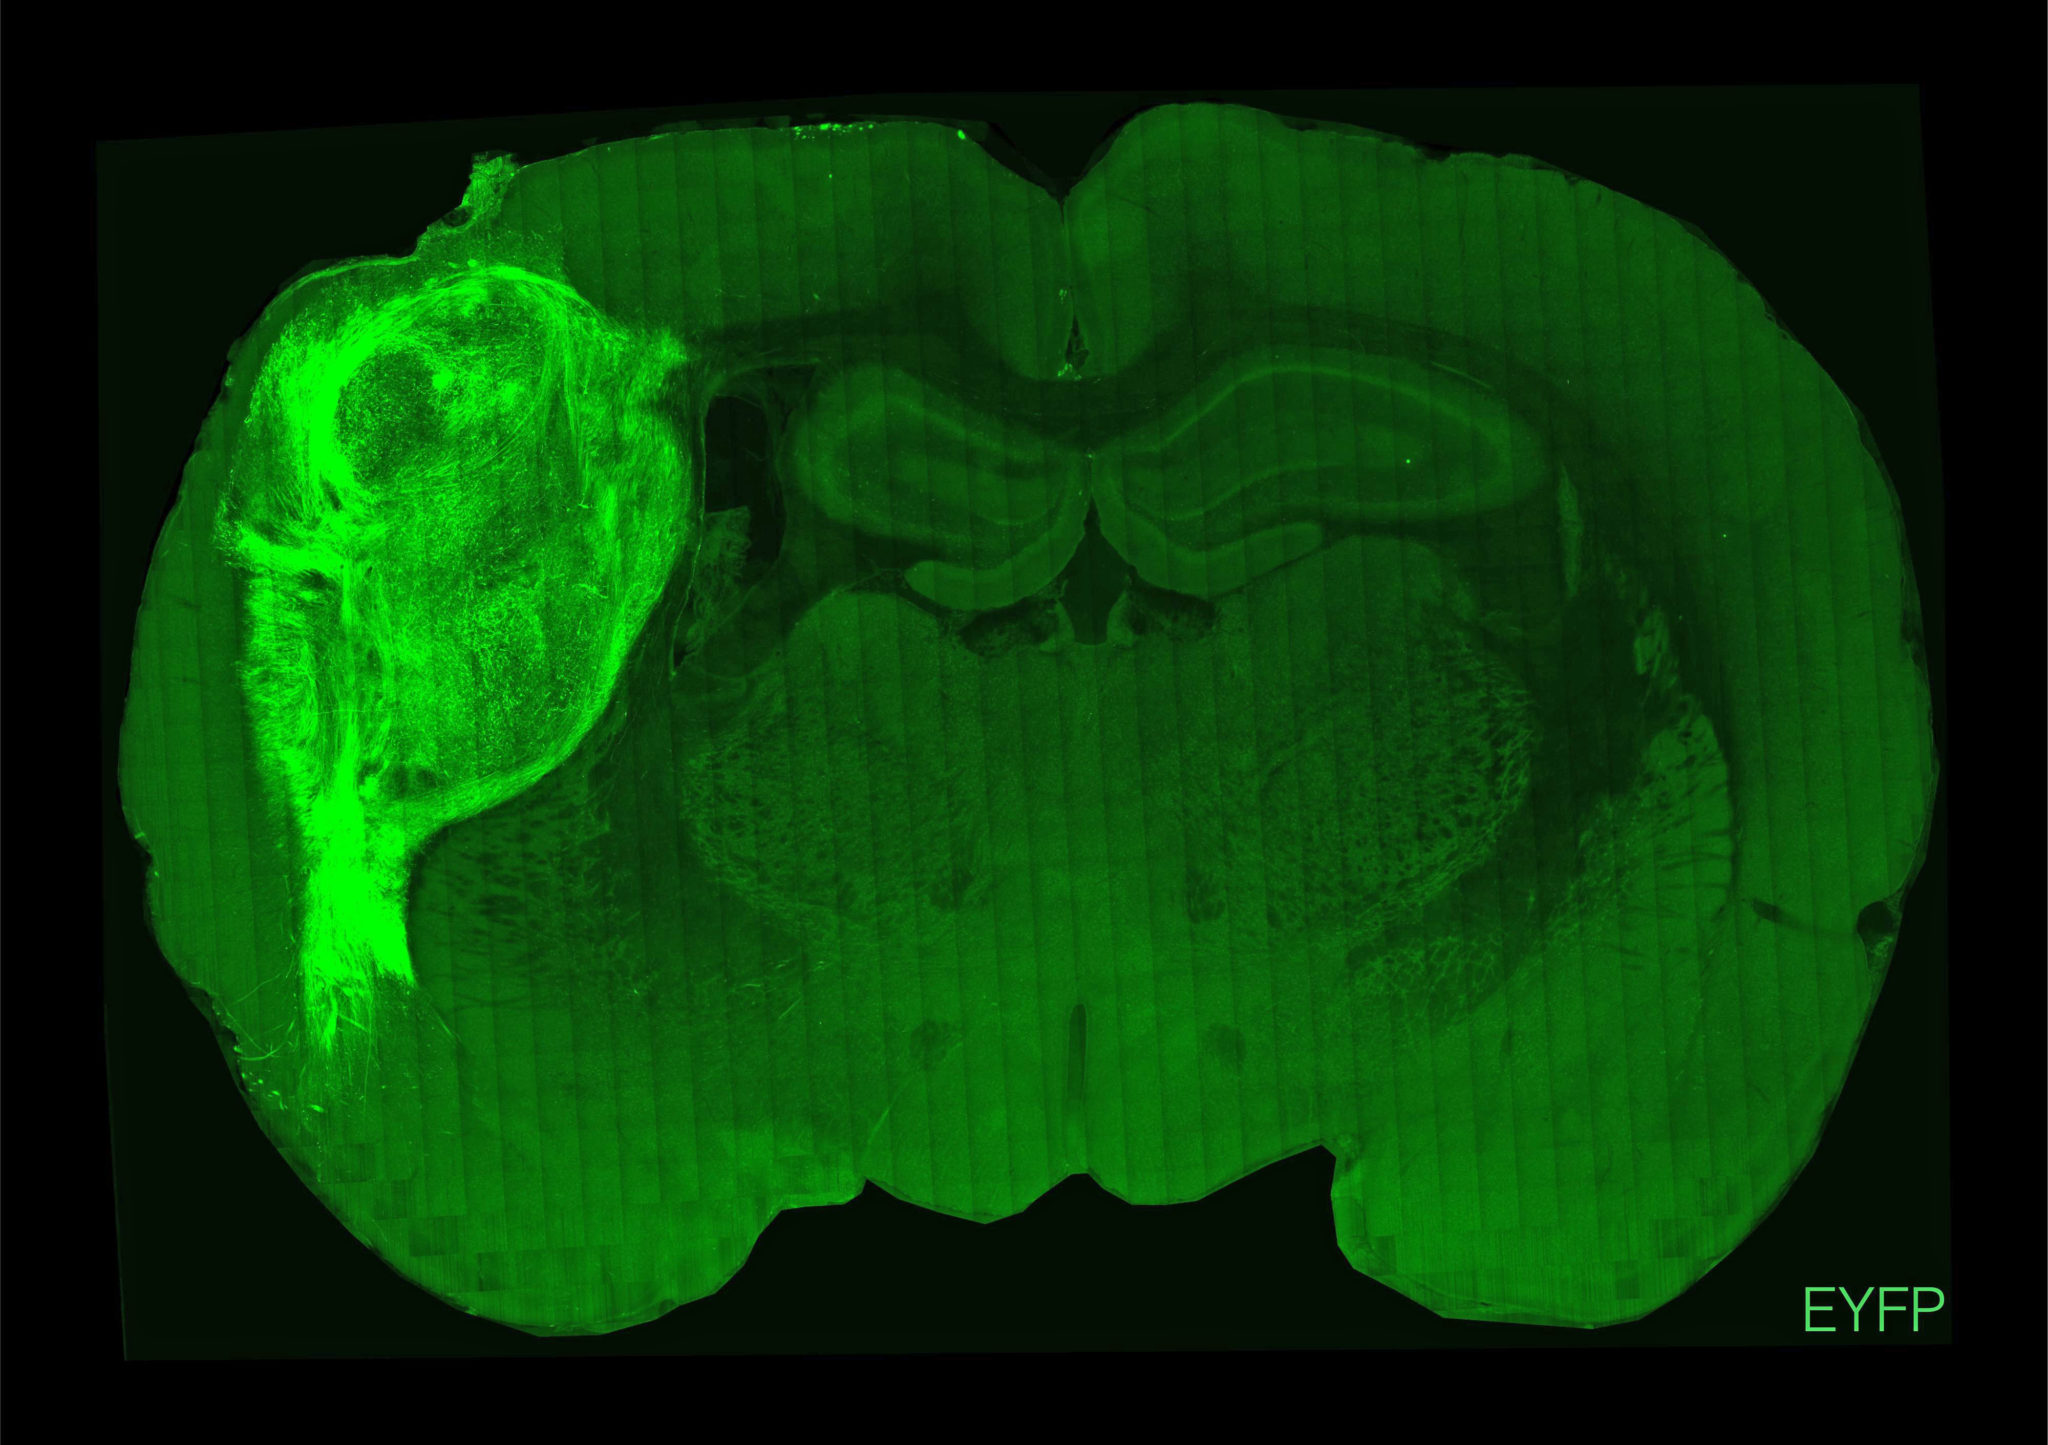

Οι εγκέφαλοι των ζώων ενσωμάτωσαν ομαλά το μόσχευμα, το υποστήριξαν με νέα αιμοφόρα αγγεία και το προστάτευσαν με ανοσοκύτταρα. Έτσι οι ανθρώπινοι νευρώνες πολλαπλασιάστηκαν και τελικά κάλυψαν περίπου το ένα τρίτο του ενός ημισφαιρίου του εγκεφάλου των ζώων. Όπως είπε ο Πάσκα, “ήταν σαν να προσθέτεις άλλο ένα τρανζίστορ σε ένα ηλεκτρονικό κύκλωμα”. Τελικά οι ανθρώπινοι νευρώνες σχημάτισαν συνδέσεις (συνάψεις) με τα εγκεφαλικά κυκλώματα των αρουραίων και κατέληξαν να επηρεάζουν τη συμπεριφορά τους, ενώ δεν φάνηκαν κάποιες παρενέργειες στα ζώα.